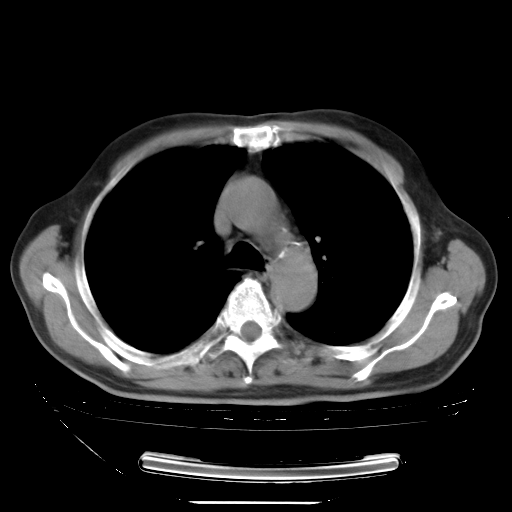

今天复查肺部CT,发现双肺广泛磨玻璃样改变。所以我把3月19日和5月9日相隔50天的肺部CT上传。请大家会诊。

5月9日肺部CT(在4月27日齐鲁医院肺部CT描述部分肺组织磨玻璃样改变,12天后肺组织广泛磨玻璃样改变)

2009年5月9日肺部CT

大致读了系列胸部CT:纵隔窗无明显异常,肺窗:从4、27至今:主要是双肺中下野外带可见毛玻璃样改变,目前处于急性肺泡炎阶段,至于原因考虑1、结替组织或胶原血管性疾病所致?2、恶性疾病如恶组在肺部所致的表现或细支气管肺泡癌?3、药物或其它原因如肺蛋白沉着症所致肺泡炎目前不太可能?总之,明天就去请我院的呼吸科、感染科、血液科和临免专家会诊哈。